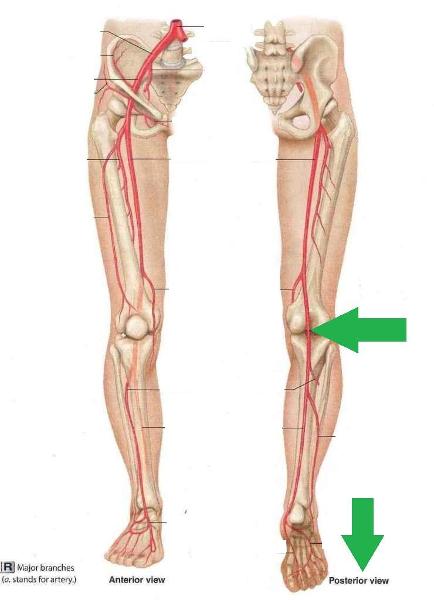

Anterior tibial artery/vein

Posterior tibial artery/vein

Common iliac artery/vein

Femoral artery/vein

Great saphenous vein

Internal/external iliac artery/vein

Popliteal artery/vein